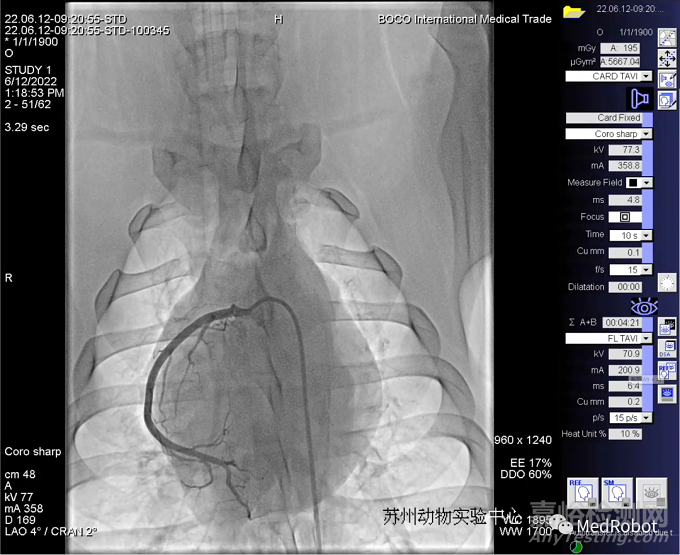

近日,微亞醫(yī)療科技(蘇州)有限公司(以下簡(jiǎn)稱“微亞醫(yī)療”)全自主研發(fā)的“微亞冠通”微創(chuàng)血管介入手術(shù)機(jī)器人成功完成國(guó)內(nèi)首例異地遠(yuǎn)程經(jīng)皮冠狀動(dòng)脈造影及治療動(dòng)物實(shí)驗(yàn)。中國(guó)醫(yī)學(xué)科學(xué)院阜外醫(yī)院竇克非教授在北京遙操作位于蘇州的機(jī)器人對(duì)動(dòng)物進(jìn)行了冠脈造影和支架置放手術(shù)。本次動(dòng)物實(shí)驗(yàn)的成功標(biāo)志著“微亞冠通”血管介入手術(shù)機(jī)器人已完全具備跨院遠(yuǎn)程手術(shù)能力,相關(guān)技術(shù)達(dá)到國(guó)際領(lǐng)先水平。

本次動(dòng)物實(shí)驗(yàn)成功完成了兩例實(shí)驗(yàn)用豬的左、右冠狀動(dòng)脈造影、并于一例實(shí)驗(yàn)用豬的左冠血管植入支架。實(shí)驗(yàn)中分別采用多種器械組合進(jìn)行了相同術(shù)式操作,均取得成功,充分驗(yàn)證了微亞醫(yī)療血管介入機(jī)器人遠(yuǎn)程手術(shù)的安全性、穩(wěn)定性和場(chǎng)景適用性。